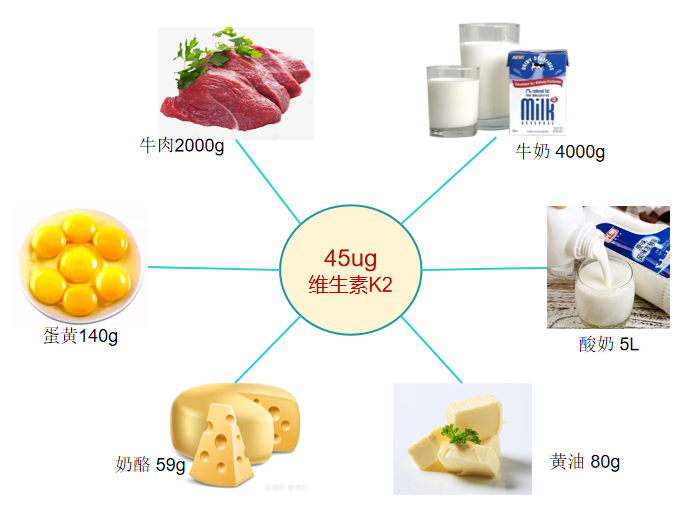

每获取45ug维生素K2所需食物的量

在日本调查发现,食用纳豆的东京女性血液中维生素K的含量比不食用纳豆的伦敦女性高15倍。须见洋行及其同事研究证实,进食100克纳豆,4小时后血液中维生素K2的浓度最高可达原来的54倍。

维生素K2较多存在于发酵食物中,其中纳豆含量最高,其他食物含量甚微。每天食用10克纳豆就可为机体提供足够的维生素K2。